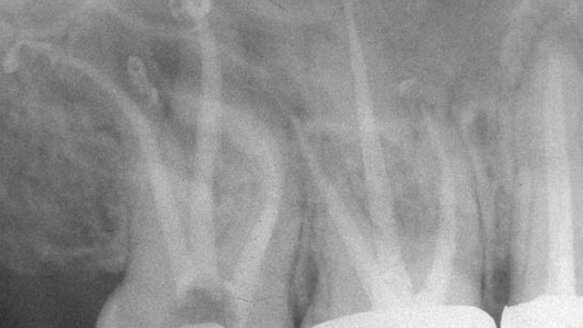

Rotation around a curve creates cyclic fatigue, shortening the life of the NiTi instruments, with cyclic fatigue accelerated the greater and the more abrupt the curve being negotiated[2]. Compensation for this vulnerability comes in two forms. The poorly designed K-files (Fig. 1) may be used to further shape the canals before switching to rotary NiTi or the NiTi instruments may shape more conservative preparations, not based on the biologic needs of the canal, but the metallurgic limitations of the NiTi instrument.